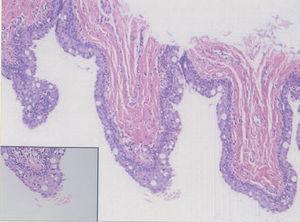

Fig. 2.--Alternancia de epitelio escamoso estratificado con queratinización infundibular, mucoso no queratinizante y glandular. (Hematoxilina-eosina, x100.)

El estudio histopatológico de una de las lesiones evidenció la presencia de una cavidad quística unilocular, localizada en la dermis profunda, sin conexión epidérmica. El epitelio de revestimiento de la cavidad estaba formado por una doble capa celular. Presentaba en algunas zonas distintos patrones de diferenciación, que se observaban en continuidad unos de otros (figs. 2 y 3).

La lesión quística se hallaba revestida por un epitelio escamoso estratificado con queratinización infundibular y, ocasionalmente, por un epitelio seudoestratificado de aspecto glandular, formado por células cilíndricas de citoplasma claro, proteínas amiloides séricas positivas, con imágenes ocasionales sugestivas de secreción por decapitación.

Ocasionalmente se podía observar la presencia de un epitelio escamoso sin queratina ni capa granulosa, sugestivo de erosión mecánica (cercano a zonas de laceración), con presencia de reacción gigantocelular a cuerpo extraño.